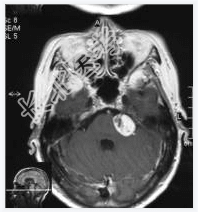

- [材料题] 患者,女性,71岁,因耳鸣、双下肢乏力4~5月,进行性发展入院。体检:左耳听力下降,行走碎步,四肢肌力Ⅴ级,肌张力略高。临床诊断:帕金森综合征。做头颅MRI检查。

- 简答题1、请问该病例诊断是什么?

- 简答题2、请问诊断依据是什么?

- 简答题3、请问鉴别诊断有哪些?

- 简答题4、左听神经鞘瘤的典型症状是什么,以及它是如何影响患者的听力和平衡功能的?

- 简答题5、左听神经鞘瘤治疗措施有哪些?